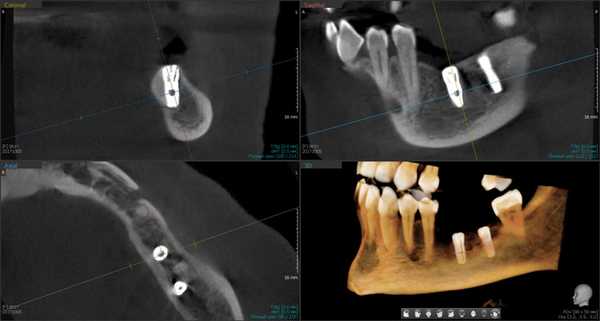

Результаты рентгенологического исследования показали, что дентальная объемная томография наиболее информативный метод при оценке степени повреждения нижнего альвеолярного нерва. Истинное трехмерное изображение исследуемого объекта и вращение его вокруг любой из трех осей на 360 градусов, позволяют визуализировались положение имплантата по отношению к нижнечелюстному каналу и документировать степень его повреждения. Программное обеспечение Ez3D-iV4.3.0 от Vatech предполагает огромный функциональный набор. Применительно к диагностике повреждения нерва после имплантации в данном софте в режиме высокого качества разрешения возможна трехпроекционная реконструкция, с возможностями переориентации осей, с измерением габаритов объекта исследования в масштабе 1:1(рис.3).

Рис.3 Конусно-лучевая компьютерная томография от Vatech. На коронарной проекции определяется верхушка дентального имплантата 3.6, перфорирующая медиальную стенку нижнечелюстного канала.